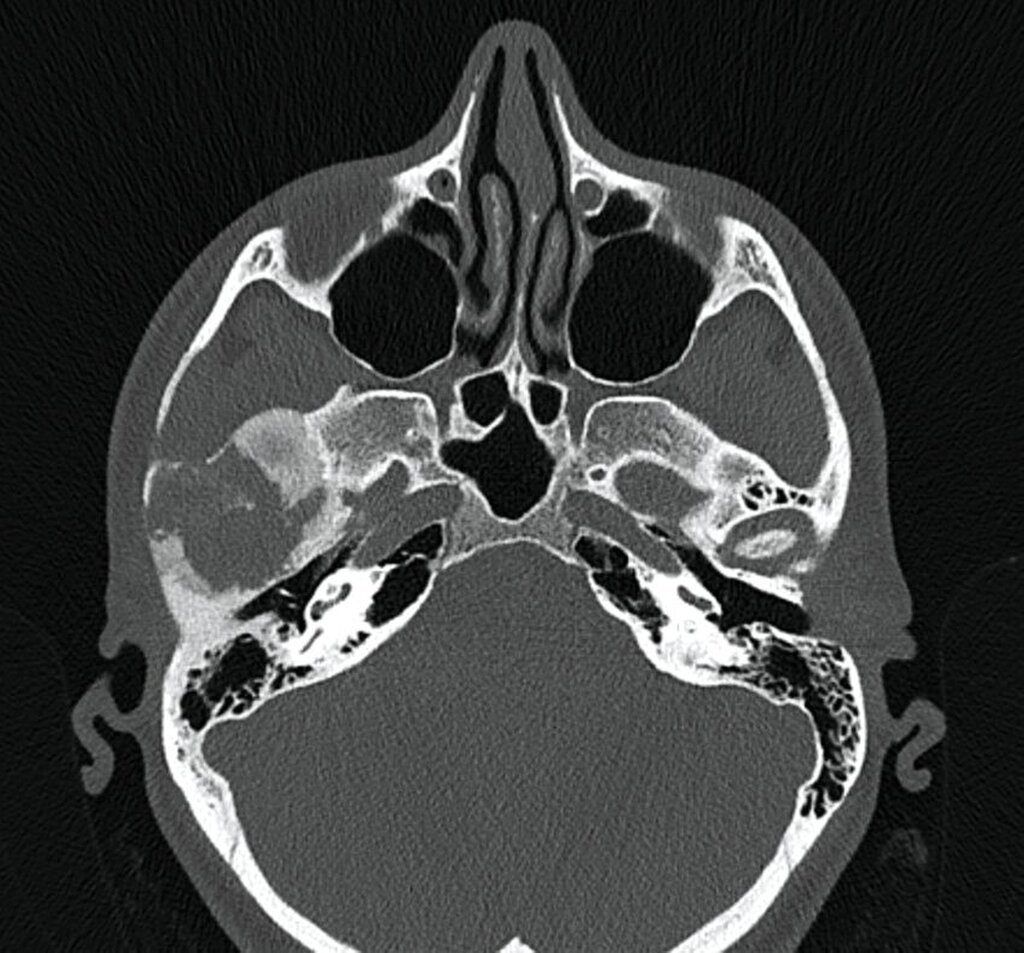

Im MRT und CT zeigte sich eine expansiv wachsende, überwiegend mattglasartige Knochenveränderung mit osteolytischen Anteilen und Unterbrechungen der Knochenstruktur, insbesondere in den unteren Partien nahe dem Kiefergelenk. Die Läsion war mit vermehrter intraossärer Kontrastmittelanreicherung assoziiert, was für eine fibröse Dysplasie spricht. Das Kieferköpfchen war abgeflacht, und es lag eine geringe Flüssigkeitseinlagerung im Kiefergelenk vor. In der Bildgebung fanden sich keine Hinweise auf eine Beeinträchtigung der umliegenden Foramina oder angrenzender Knochenstrukturen wie des Keilbeins (Abbildung 1).

Die Diagnose der CFD basiert in der Regel auf bildgebenden Verfahren, insbesondere der Computertomografie. Typisch ist dabei das sogenannte milchglasartige Erscheinungsbild des geflechtartigen Knochens, wie im vorgestellten Fall. Allerdings können die Läsionen sehr unterschiedlich erscheinen und auch sklerotische, zystische oder gemischte Strukturen aufweisen. Zu den differenzialdiagnostischen Überlegungen zählen unter anderem Meningeome, die Paget-Krankheit, niedriggradige Osteosarkome sowie verschiedene benigne fibroossäre Läsionen. Bei CFD-Läsionen mit maligner Entartung werden in der Bildgebung eine Destruktion der Kortikalis und eine Zunahme der Ausdehnung ins Weichgewebe beschrieben [Sun et al., 2014].